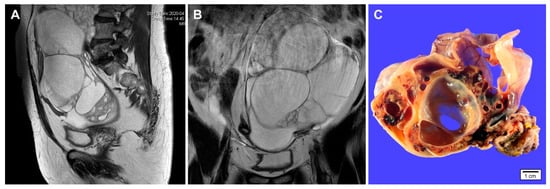

Imaging and gross findings of gynandroblastoma. (A,B) a 65-year-old woman presented with an abdominal mass. Abdominopelvic magnetic resonance imaging reveals a 20 cm multiseptated cystic mass arising from the left ovary. No evidence of abdominopelvic peritoneal seeding, lymph node enlargement, or hematogenous metastasis is identified. Preoperative laboratory test showed a slight elevation of serum CA 125 level (37.1 U/mL). The serum CA 19-9 level was within normal range (32.1 U/mL). (C) Grossly, the cut section of the ovarian tumor shows variable-sized, thin-walled cystic spaces. Solid areas show yellow-to-tan tumor tissue with hemorrhagic spots. The inner surface of cystic lesions is relatively smooth and glistening.